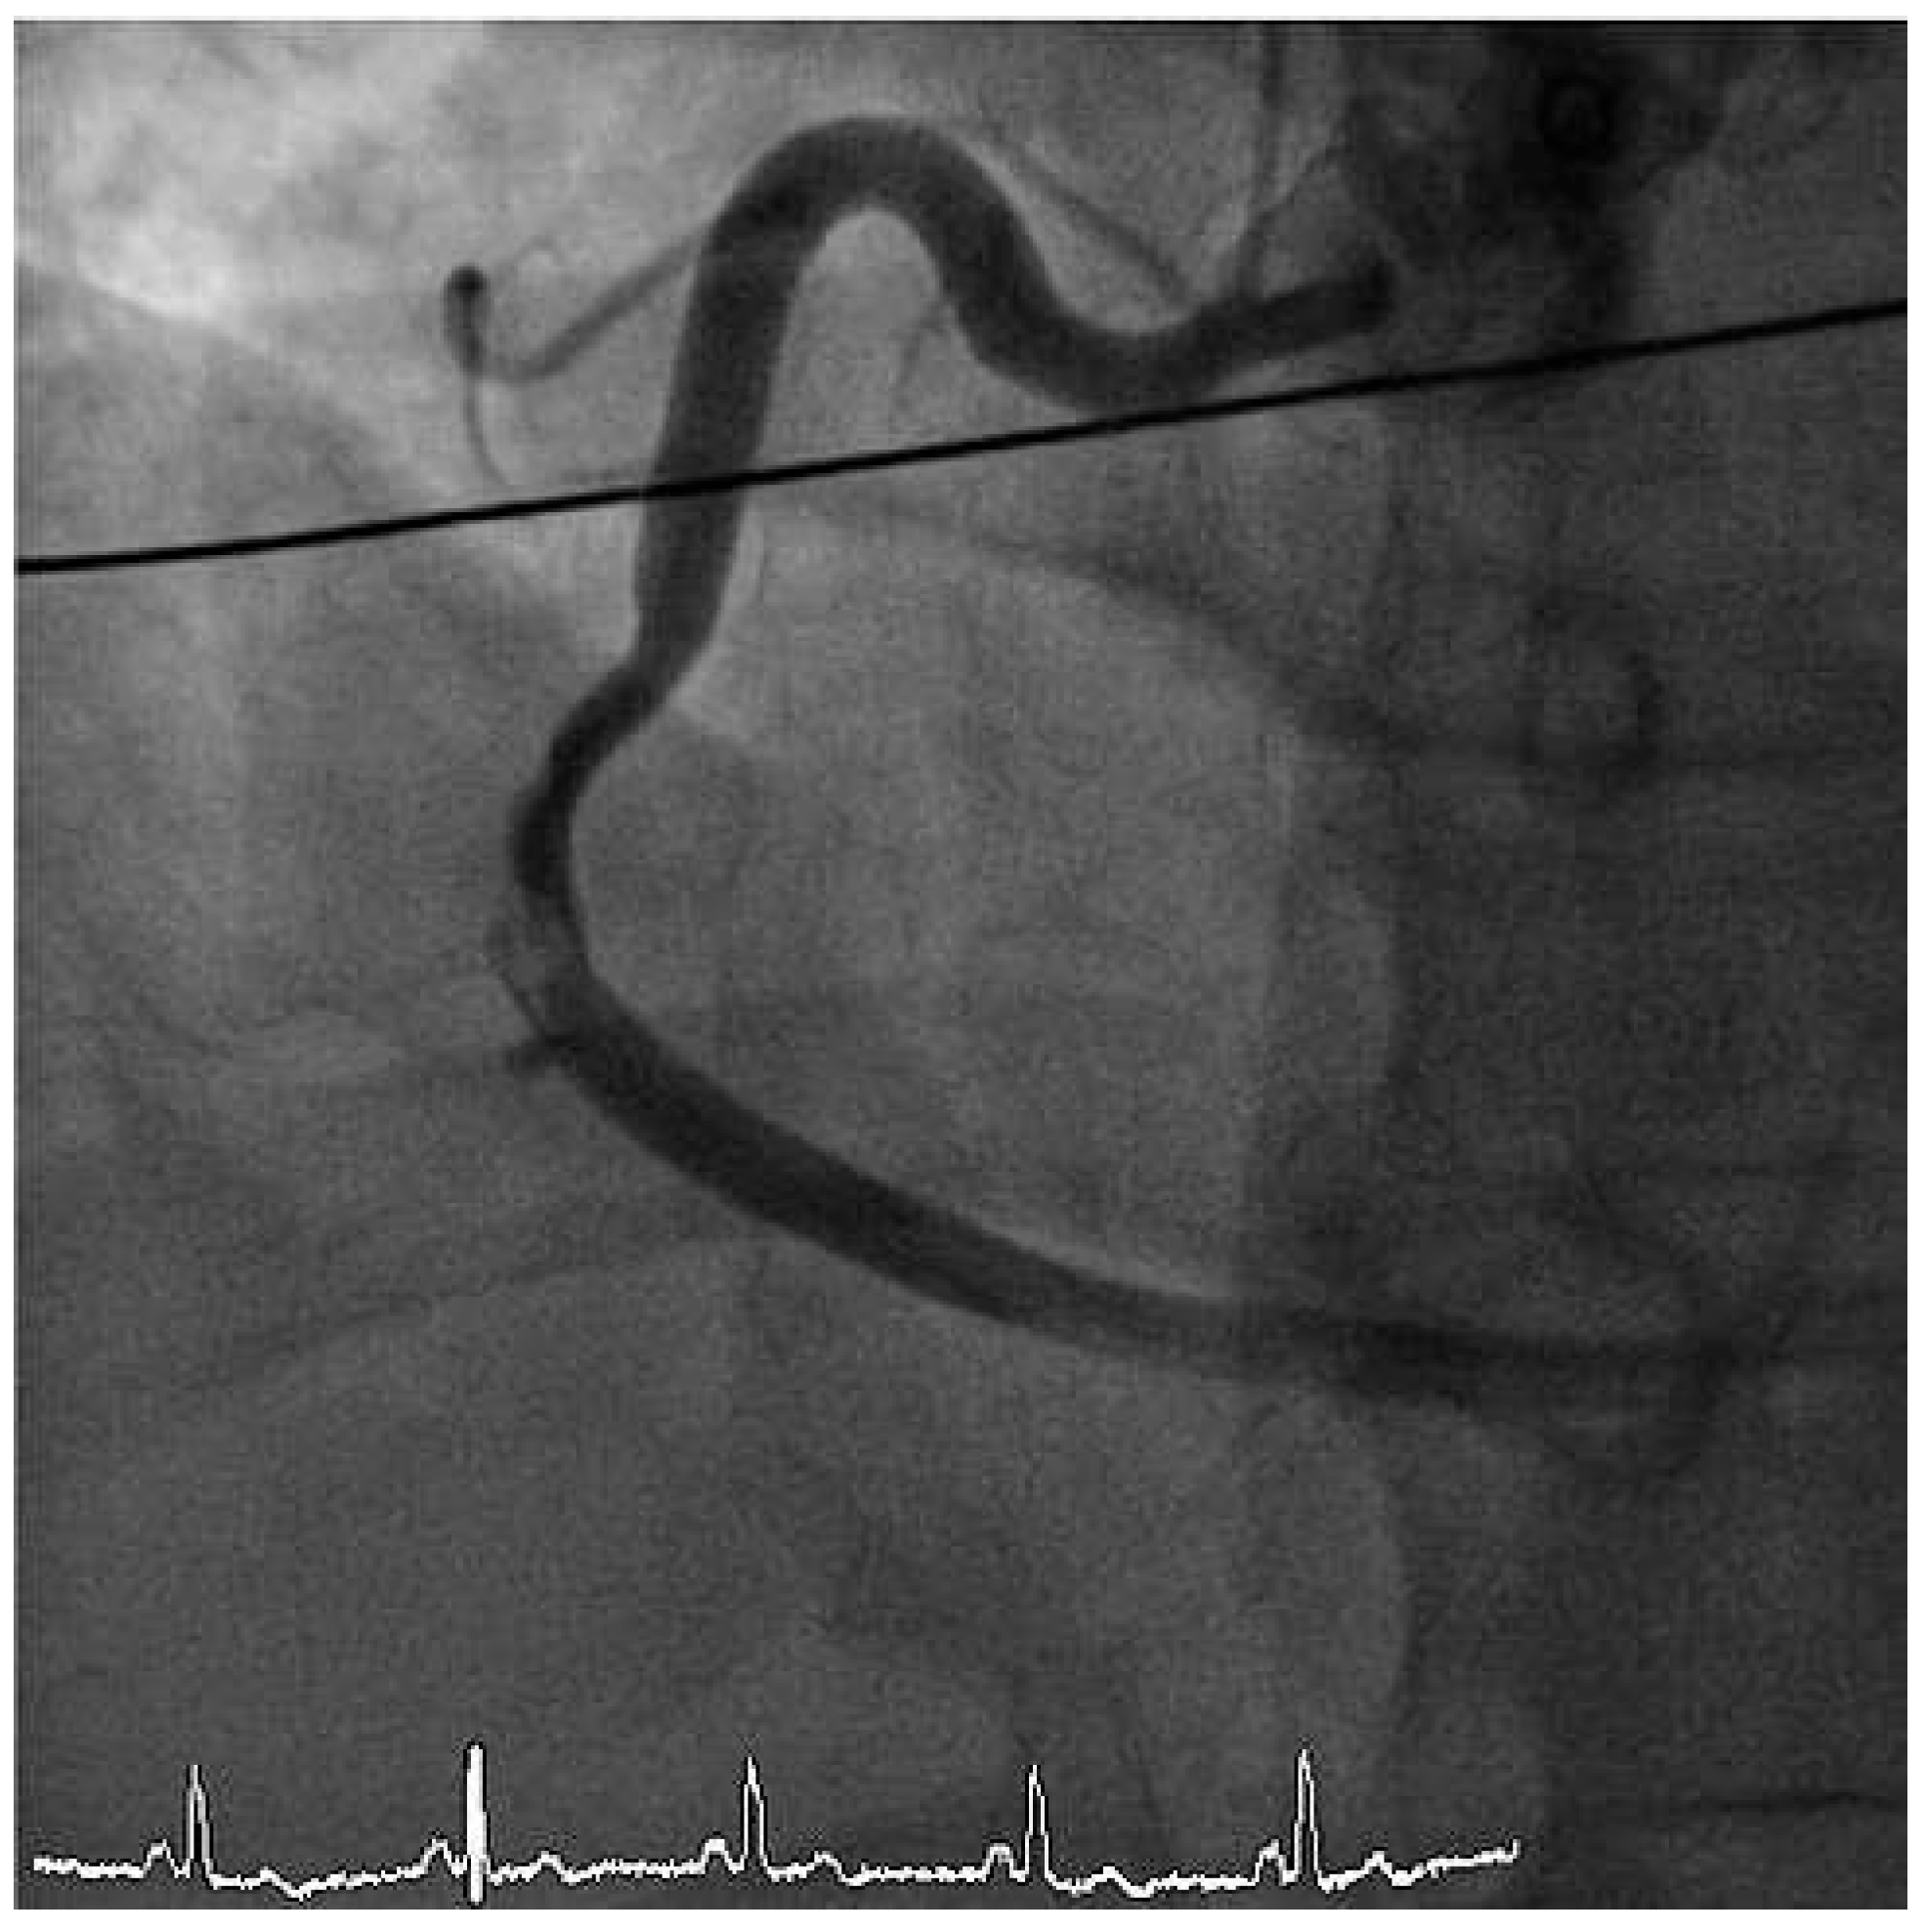

Furthermore, the right coronary artery showed a subtotal thromNo botic occlusion (Figure 3). Prior to the local treatment, a bolus of heparine 5000 IU and Abciximab were administered due to the heavy thrombus load. Thrombus aspiration was performed using an aspiration-catheter (Export AP, Medtronic) in all three coronary vessels. Due to persistent thrombotic material in the mid LAD, two low-pressure balloon inflations were done with a good end result (Figure 4 and Figure 5). There were no periprocedural complications. A treatment with life-long aspirin, one-year prasugrel, Betablocker and ACE-Inhibitor was initiated. The next day, a transesophageal echocardiography demonstrated improved LV-function (EF 50%) without evidence for an intracardiac thrombus or a patent foramen ovale (PFO).

Figure 3. LAO cranial view showing right coronary artery with subtotal thrombotic occlusion.